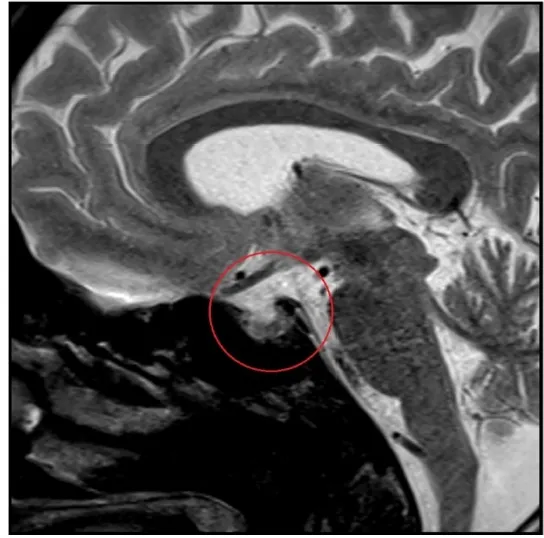

Uma causa incomum de hematúria glomerular intermitente!

Hematúria pós infecção, caso clínicos para auxiliar no entendimento de causas glomerulares comuns e raras...